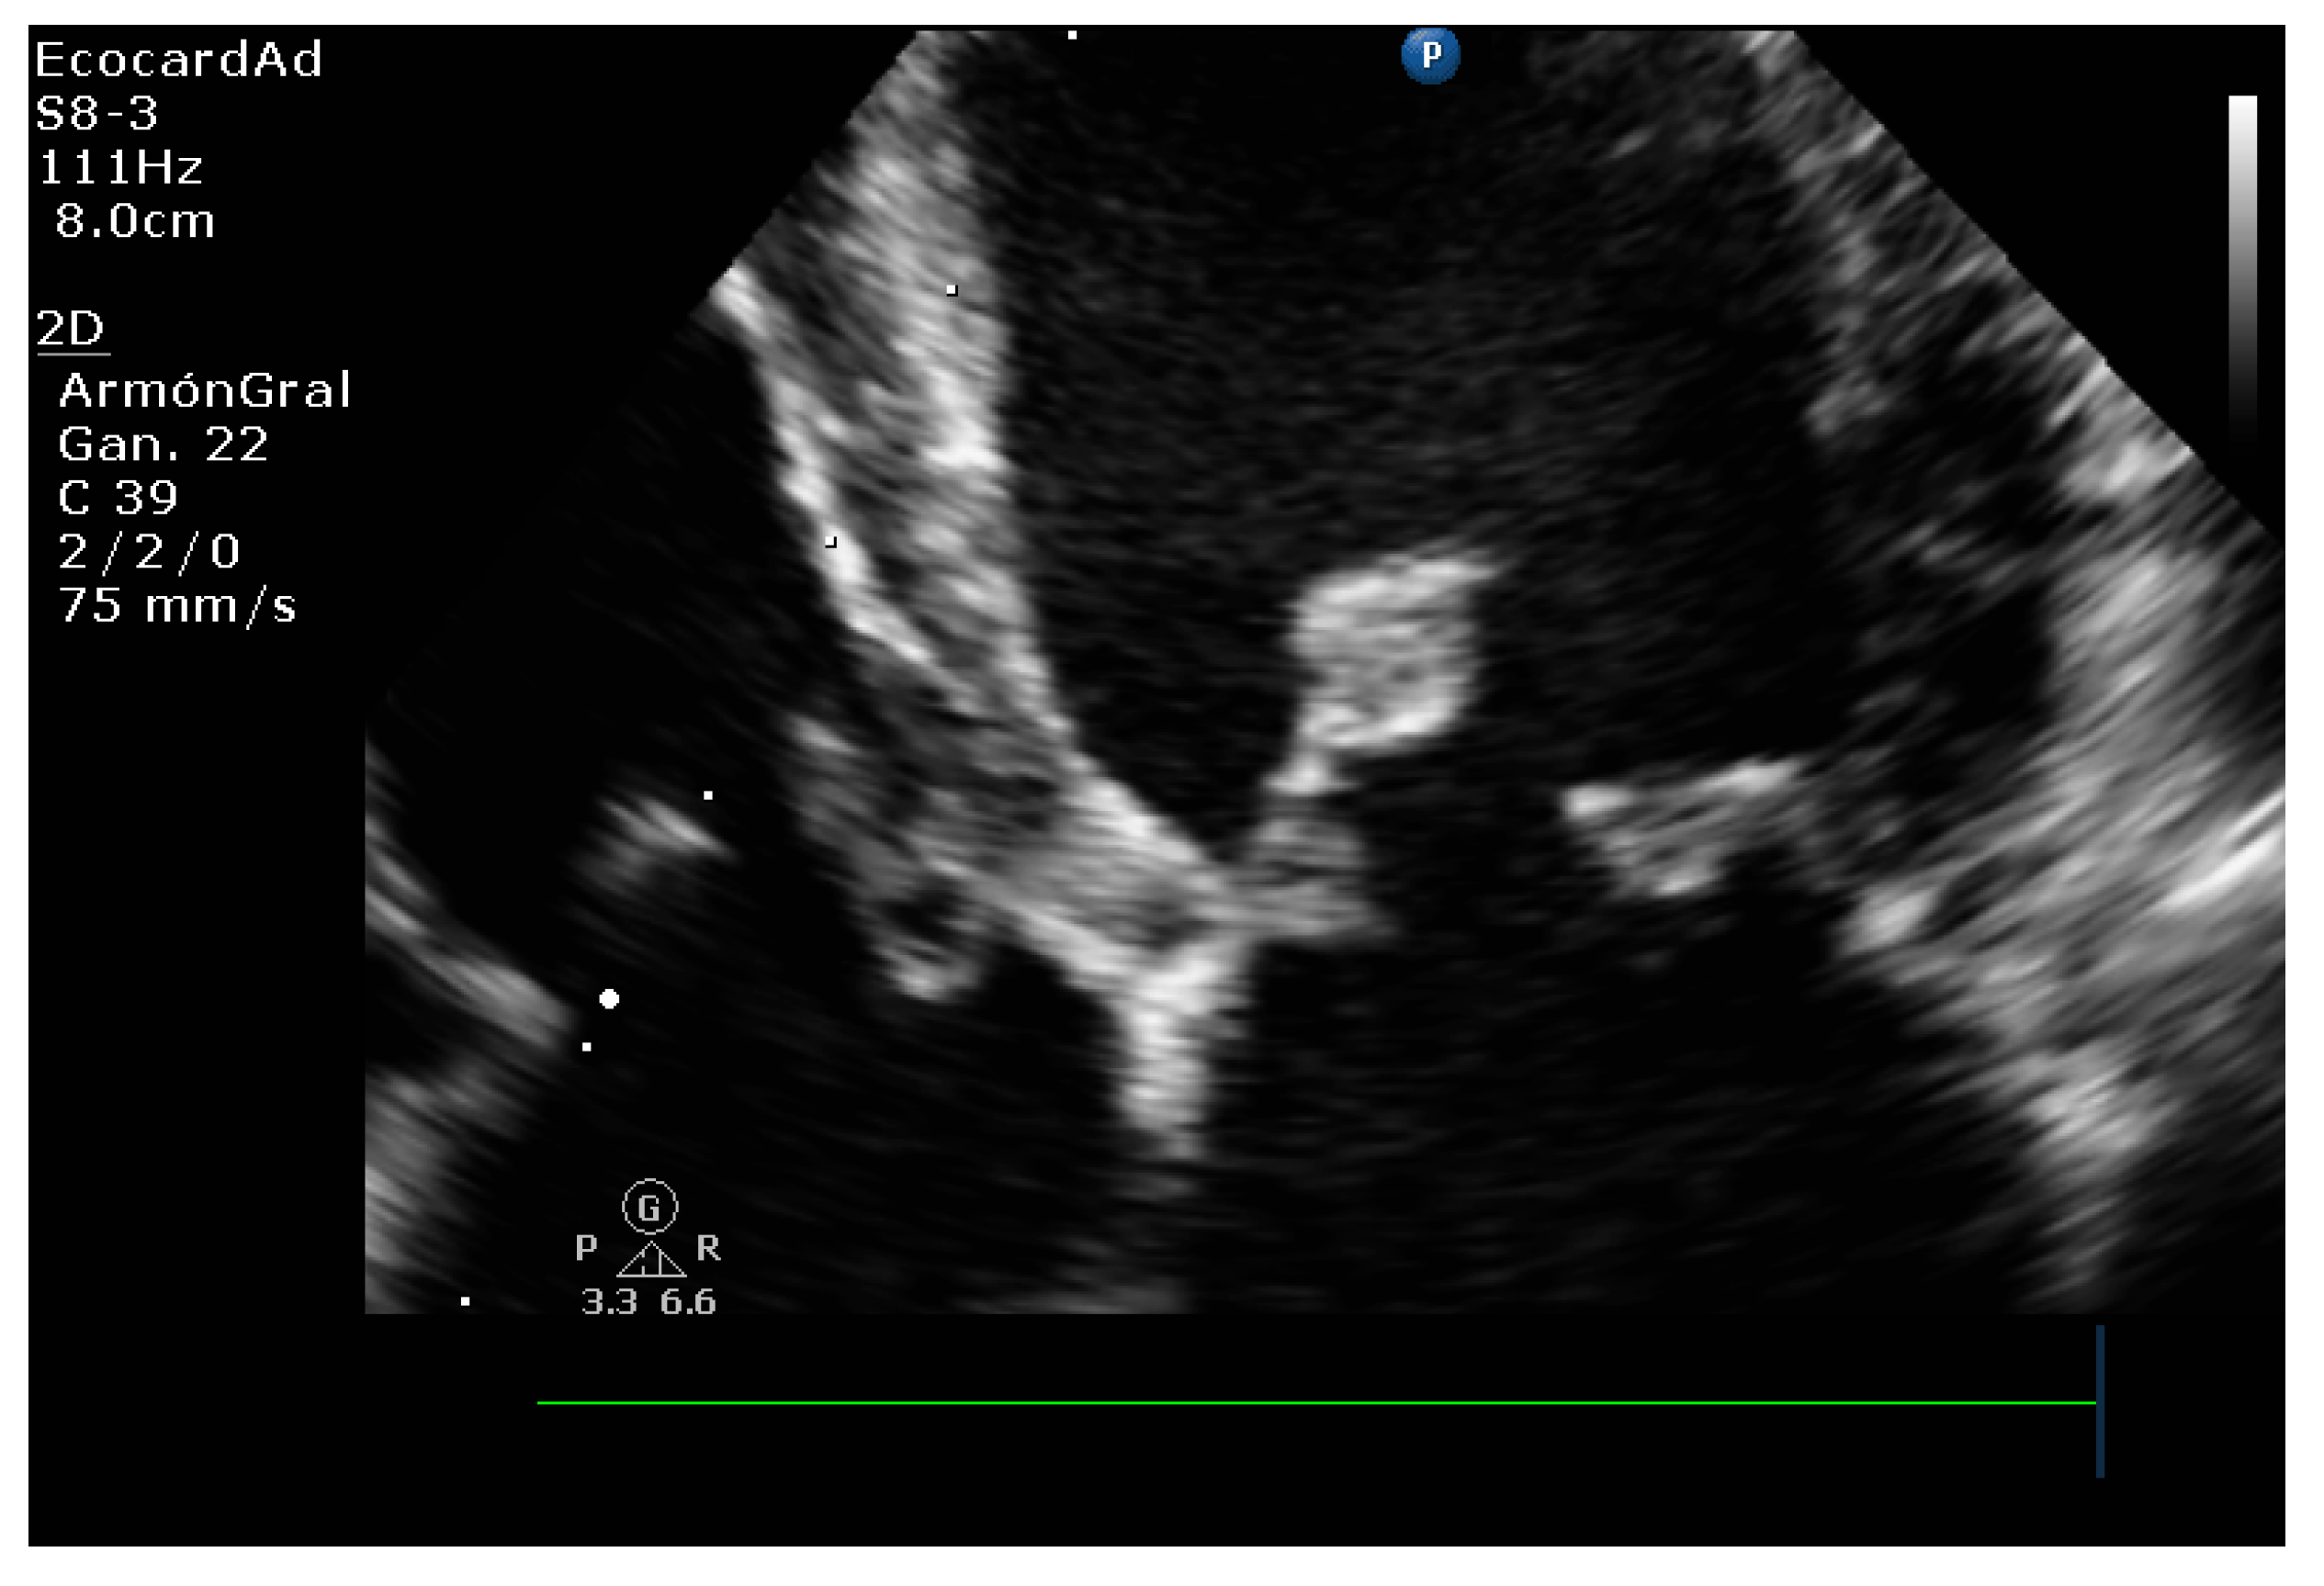

4.3. Canine Myxomatous Mitral Valve Disease. Comparative Transthoracic Echocardiography with Human Mitral Valve Prolapse

4.8.3. Degree of Myxomatous Degeneration

4.8.4. Mitral Valve Prolapse

4.8.5. Vmax Wave E